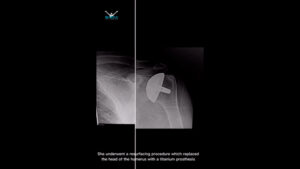

Patient Returns To Swimming After Having Both Shoulders Replaced!

«This patient had bilateral shoulder replacements (shoulder resurfacing)» Since then she’s been able to return to #swimming and has no more pain 🙌